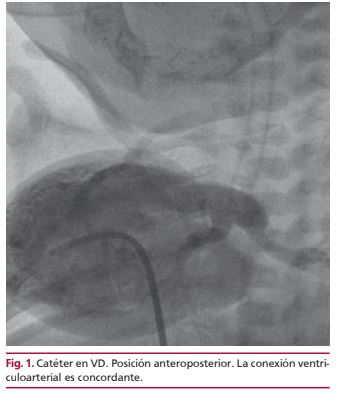

IMÁGENES EN CARDIOLOGÍA